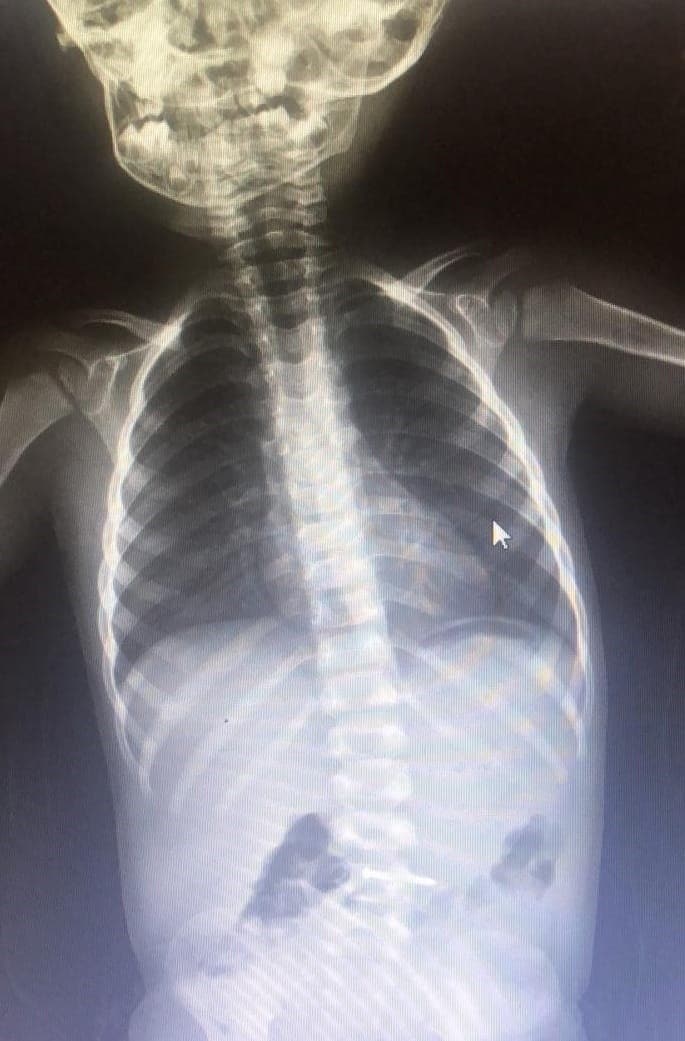

Olay, Mesudiye Mahallesi Sakin Sokak’ta meydana geldi. 2 yaşındaki Asil K., evde oynarken yerde bulduğu çiviyi ağzına atıp yuttu. Olayı gören ailesi, küçük çocuğu hemen özel araçla İnegöl Devlet Hastanesi’ne götürdü. Yapılan tetkiklerde çivinin midesinde olduğu tespit edilen çocuk, ambulansla Bursa Yüksek İhtisas Eğitim ve Araştırma Hastanesi’ne sevk edildi.